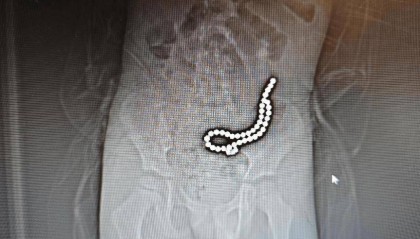

整整37颗!云南4岁孩子身体里取出……医生紧急提醒!

磁力珠色彩绚丽、玩法多样,深受小朋友喜爱。但如果误食,后果却会很严重。 近日,丽江市人民医院接收了一...

欧意全球站 2025-06-18 34